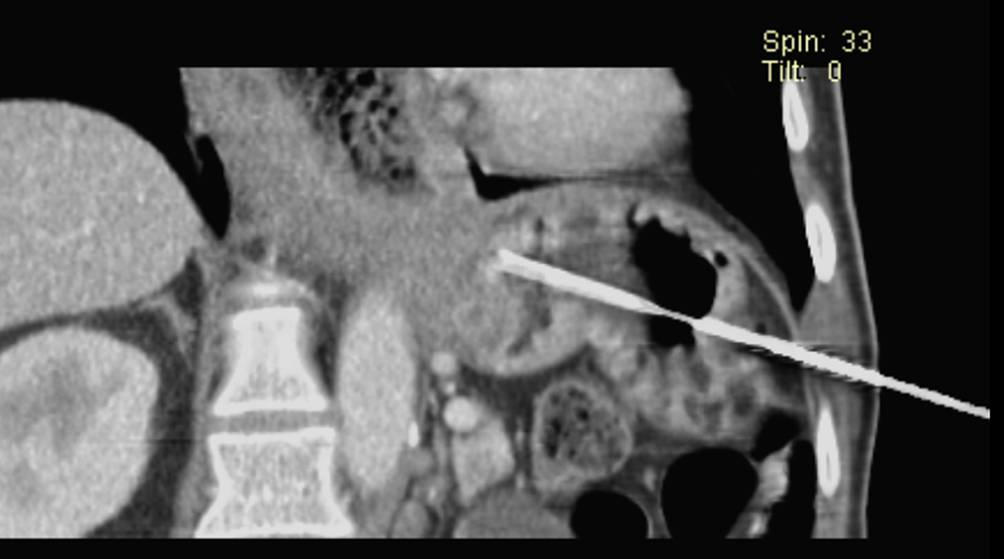

Abb. 4

CT-gezielte Biopsie des Tumoranteils an der Cardia: Man erkennt die Biopsienadel von interkostal transgastrisch mit der Spitze an der Cardia